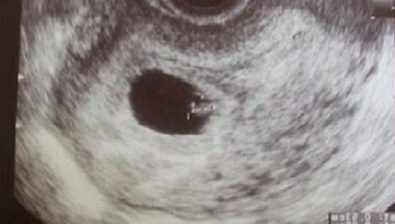

Ultrasound at 7 Weeks

Along with the tiny little arm and leg buds protruding, your baby is also developing the cerebral hemispheres of the brain. Eyes and nostrils are growing, as well.

While still looking slightly tadpole-ish, your baby has a clearly defined heart bulging from the chest.

All of these wonderful developments won’t be visible on an ultrasound, but be confident that the little bean on the screen is growing by leaps and bounds!